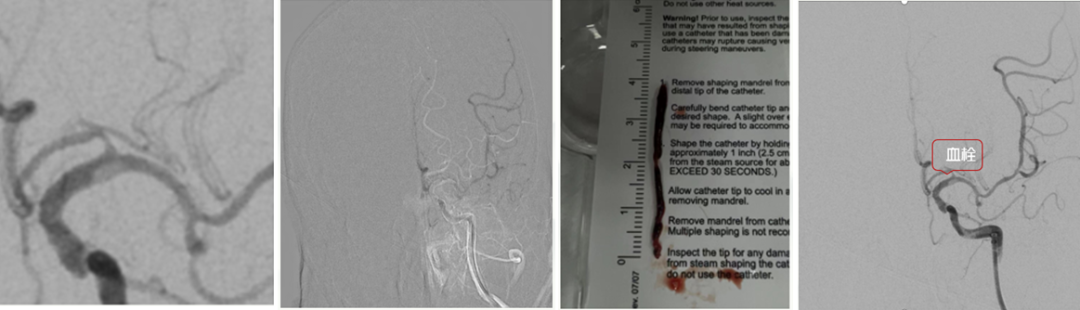

DSA

病历夹什么径技·第151期|串联营病历夹:京广连营_https://www.jmylbn.com_新闻资讯_第8张

病历夹什么径技·第151期|串联营病历夹:京广连营_https://www.jmylbn.com_新闻资讯_第9张

结论:左侧颈动脉起始部位出现断流,右侧颈动脉没有明显代偿,血管形态较光滑。

• 球囊4*30mm打开通道后进行造影,发现远端闭塞,考虑到其因局部血栓逃逸至远端。

• 在球囊半扩张的状态下,输送Guiding至C2段,可明显看到血栓存在。

• 将5F中间导管伸至闭塞处,抽吸泵1次抽出4cm左右血栓。

• 但在复查造影过程中发现大脑起始部位有微小血栓,选用微导管:贴近血栓处抽吸成功,且造影结果较为理想。

• 导丝回撤时发现“真凶”——颈动脉开口处C1段夹层样改变。

• 选用覆盖率较高的Carotid Wallstent支架覆盖夹层全段,维持血管重建,持续替罗非班6ml/H。